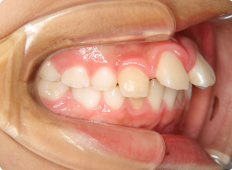

9歳男子

上の前歯が出ており、口が閉じづらい事を気にして来院されました。

上あごが突出しているため、上あごの前方成長を抑える必要があります。ヘッドギアーを夜間の寝る時間に使用して奥歯を後方へ移動します。さらに奥歯にできた隙間を利用して、ブラケットを使いながら前歯を後方へ移動します。

【治療期間】

装置装着期間1年半。

その後永久歯列完成まで成長経過観察を行いました。